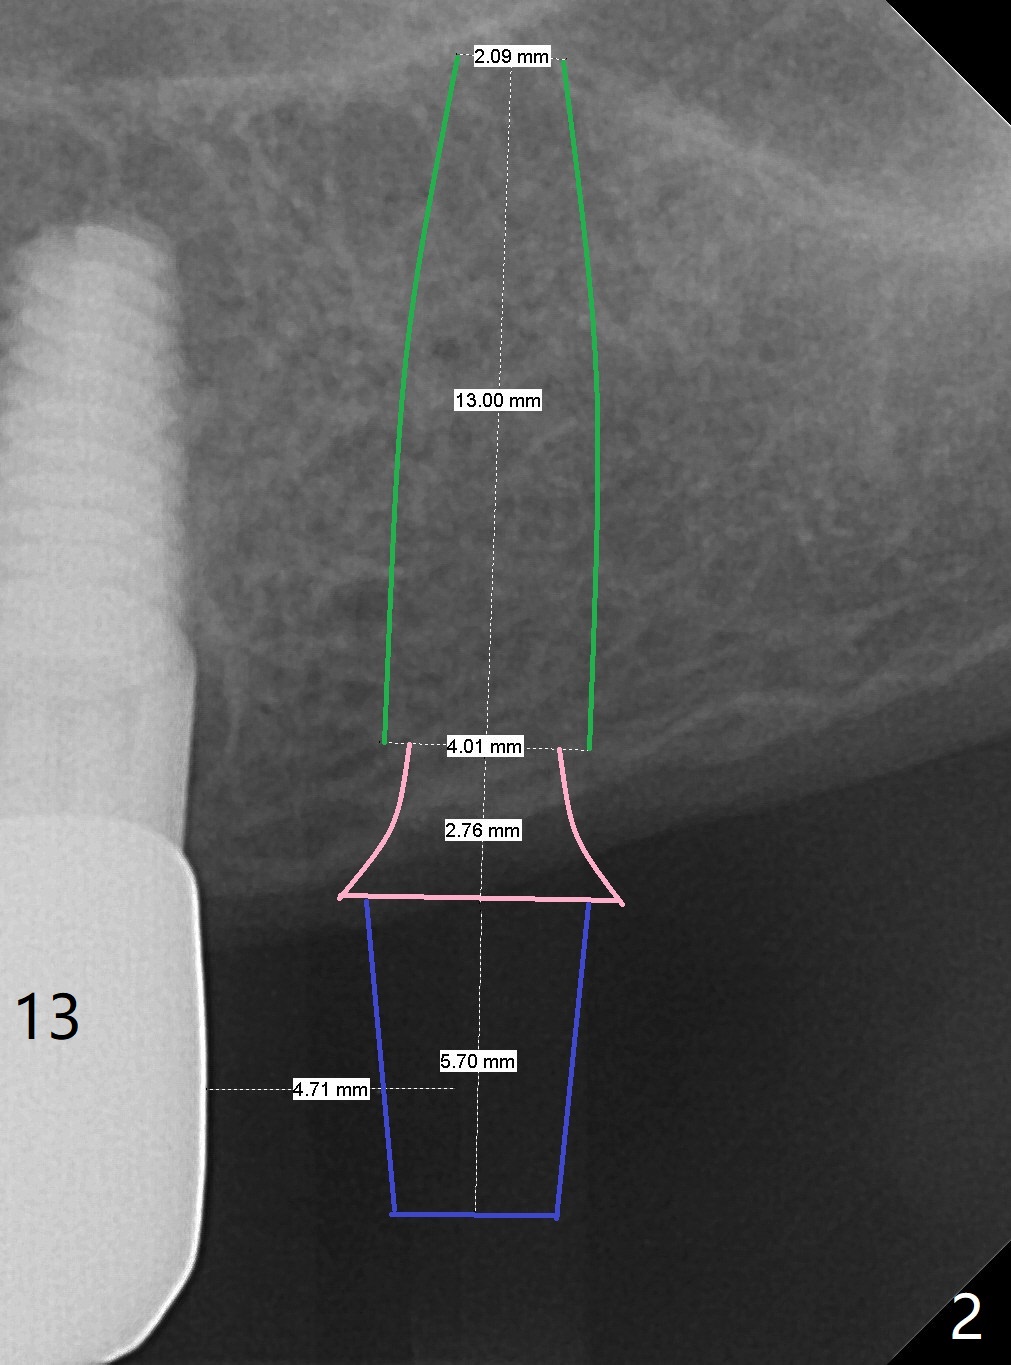

A 51-year-old woman has partial edentulism (Fig.1). The implant crown at #13 is loose 1 year 4 months post cementation (Fig.2). To prevent screw loosening for the second time, implants should be added at #14 and 19 (Fig.1). Before removing the crown at #13 for unipost bonding with V5, use Tatum bone expansion kit (BS, BB before RT). In fact, the patient agrees to have guide for #14 and 19.